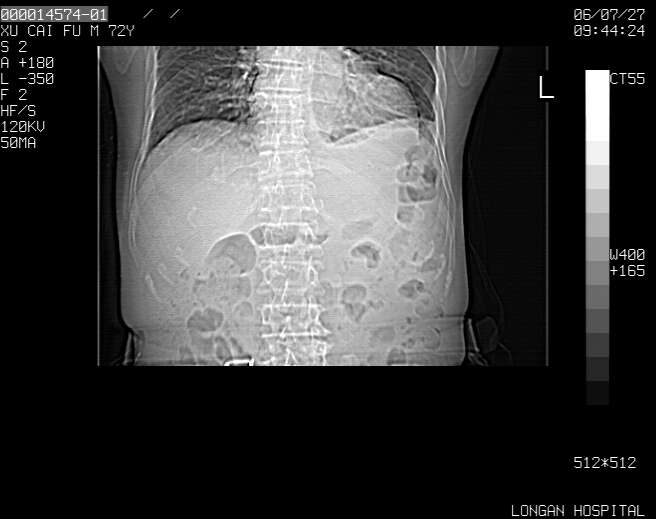

以下是引用winter在2006-7-30 20:14:00的发言:[br]1、考虑胆囊癌伴胆道侵犯并高位胆道梗阻、肝内多发转移、腹膜后淋巴结转移。[br]2、右肾轻度积水。[br]3、老人家72岁了胰腺头体尾部均较饱满,不过未见密度异常及其他异常征象。[br]4、腹水。

以下是引用jiajie在2006-7-31 7:10:00的发言:[br]考虑肝转移瘤,腹膜后淋巴结增大。[br]胃癌不能除外,建议胃镜检查。